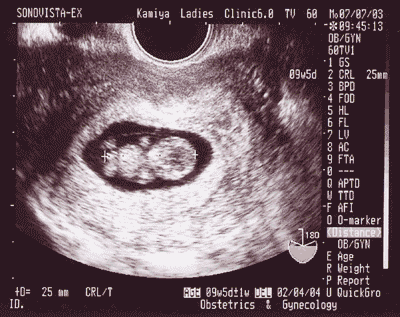

超音波写真の数字で読み取る 赤ちゃんの成長ぶり

黒い背景に、よく意味の分からないアルファベットや数字、記号が沢山並んでいる超音波写真。この写真の中に、実はいろいろな情報が詰まっています。内容を理解すれば赤ちゃんの成長ぶりがわかって感動もひとしおです。

超音波検査でもらえるエコー写真とは

超音波検査は、超音波に強く反射する“骨”は白く写り、反射しにくい血液や羊水は黒く写る仕組みになっています。プローブを当てた部分から真っ直ぐ輪切にした状態の断面を映し出しているため、プローブを当てる角度や位置によっても赤ちゃんの見え方は変わってきます。お医者さんによってはママがわかりやすいように見やすい写真を撮ってくれる場合もあるようなので、ひとことお願いしてみてもいいかもしれません。

エコー写真の数字の意味

エコー写真の端の方に記載されているアルファベットや数字。これは出産予定日や週数、赤ちゃんの大きさなどの情報なのです。

【CRL(頭殿長)】

赤ちゃんの頭からおしりまでの長さ

【AGE(妊娠数週)】

CRLの数値から計算した妊娠週数です。〇W△Dは〇週△日を指しています。

【BPD (児頭大横径)】

赤ちゃんの頭の横の長さ(幅)。平均値を「0」、小さめを「-」、大きめを「+」で表示しています。

【EDC(出産予定日)】

上記の数値から想定される出産予定日です。

【FL(大腿骨頂-だいたいこっちょう)】

太ももの骨の長さ。長めの値の場合、パパとママの背が高い傾向があるようです。

【AC(腹部周囲長)】

お腹まわりの長さ。実はこの数字、赤ちゃんがお腹を動かしているため、いちばん測定誤差が出やすい部分。太り気味を「+」、痩せ気味を「-」で表示しています。

【EFBW】

赤ちゃんの推定体重。妊娠週数に比して大きめを「+何週相当」、小さめを「-何週相当」と表示されます。